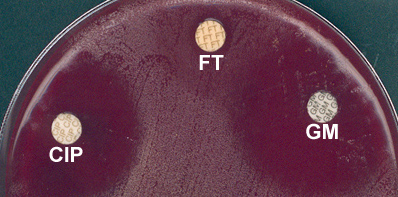

- Voici les résultats de l'antibiogramme par diffusion (méthode des disques), après 18 h d'incubation à 37°C en atmosphère ambiante, pour quelques antibiotiques :

- Fluoroquinolone: ciprofloxacine (CIP), furanes (FT) et aminoglycoside: gentamicine (GM) :